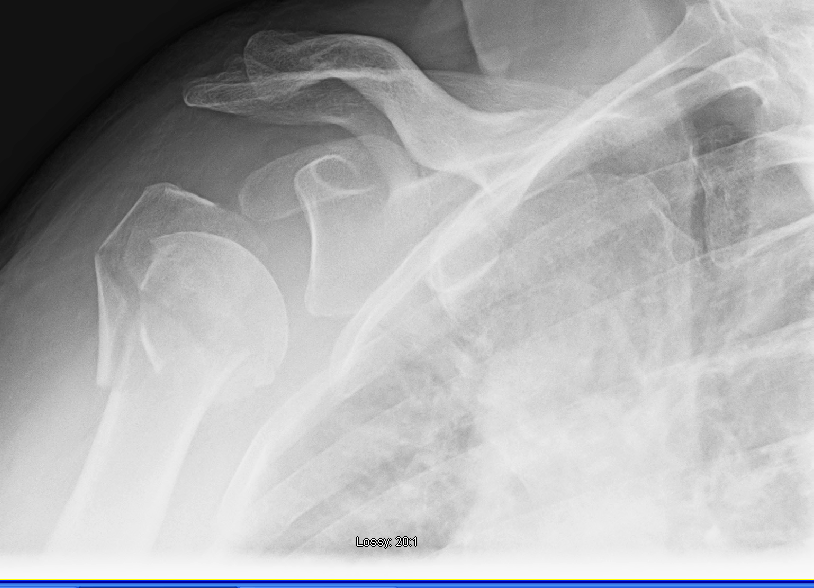

Proximal Humerus Fracture • Easy Explained OrthoFixar 2024 Split Humerus Bone Distal humerus fractures are traumatic injuries to the elbow that comprise of supracondylar fractures, single column fractures, column fractures or coronal shear. What is a humerus fracture? Fractures of the humerus are classified in one of two ways: Humerus fractures—breaks in the upper arm bone that connects the shoulder to the elbow—are generally divided into three types based where they. Split Humerus Bone.

Proximal Humerus Fractures Trauma Orthobullets Split Humerus Bone Humerus fractures—breaks in the upper arm bone that connects the shoulder to the elbow—are generally divided into three types based where they occur. Distal humerus fractures are traumatic injuries to the elbow that comprise of supracondylar fractures, single column fractures, column fractures or coronal shear. The humerus — also known as the upper arm bone — is a long bone. Split Humerus Bone.

Headsplit fractures of the proximal humerus SpringerLink Split Humerus Bone A distal humerus fracture is a break in the lower end of the humerus (upper arm bone), one of the three bones that come together to form the elbow joint. Distal humerus fractures are traumatic injuries to the elbow that comprise of supracondylar fractures, single column fractures, column fractures or coronal shear. Proximal humerus fracture or humerus shaft fracture. Distal. Split Humerus Bone.

Proximal humerus fracture Wikipedia Split Humerus Bone A distal humerus fracture is a break in the lower end of the humerus (upper arm bone), one of the three bones that come together to form the elbow joint. Proximal fractures are breaks in the top part of the humerus. A fracture in this location causes difficulty with shoulder movement, such as trying to raise the arm overhead. Identify. Split Humerus Bone.